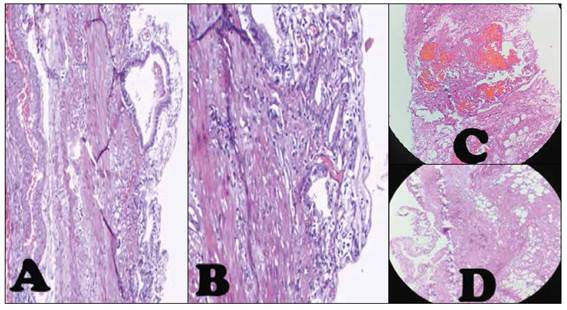

Presentamos el caso de un varón de 57 años, con antecedente de TBC pulmonar hace 20 años. Que hace 2 días presentó dolor en CSD, con irradiación a zona lumbar ipsilateral, asociado a náuseas y vómitos, y orinas oscuras. Por lo que acude a hospital, donde le realizan una ecografía abdominal, informada como VB con formación tumoral (Figura 1A), siendo referido a nuestro hospital. A su ingreso por emergencia, persistía el dolor en CSD a pesar de medicación analgésica. Al examen, paciente hemodinámicamente estable, dolor y masa palpable en CSD, y signo de Murphy positivo. La analítica de ingreso mostró una hemoblogina 14.0(VN:12-16gr/dl), hemograma 13000(VN: 5000-10000/mm3), INR 1.17, Bilirrubina total de 7.06 (a predominio directo 1.45) (VN:0.2-1.2mg/dl), fosfatasa alcalina(FA): 170(VN:27-100U/L), Gama-glutamil transferasa (GGTP): 409(VN:12-45U/L), amilasa en 66(VN: 0-120U/L), TGO 850(VN:<45U/L), TGP 980(VN:<45U/L). La ecografía fue informada como signos de CA litiásica con contenido biliar denso (Figura 1B). Se realizó una TC abdominal informada como CA litiásica con cambios inflamatorios perivesiculares y contenido hiperdenso, a considerar barro biliar o hemorragia (Figura 2A, 2B y 2C). Los marcadores tumorales (CA 125, AFP, CA19.9, CEA) y serológicos resultaron negativos; y los controles de hemoglobina y bilirrubinas disminuyeron de 14 a 12gr/dl y 7.06 a 0.66 respectivamente; además gastroenterología descartó proceso tumoral ampular. Finalmente, la colangioresonancia concluyó signos de CA litiásica con bilis de señal hemática (Figura 2D,2E y 2F). Por lo que se decide su intervención quirúrgica, realizándose una colecistectomía laparoscópica, donde se evidenció adherencias de epiplón, colon transverso, duodeno y VB, una VB gangrenada en cuerpo y bacinete conteniendo coágulos rojo oscuro y múltiples litiasis ( ). Paciente cursa con buena evolución, recibiendo antibióticoterapia y tres dosis de ácido tranexámico. Tolera dieta oral a las 8 horas de la cirugía, y dieta blanda a las 24 horas, y es dado de alta a los 2 días, tolerando dieta y sin drenajes. El estudio histopatológico reveló áreas de hemorragia, necrosis e infiltrado inflamatorio agudo, confirmando el diagnóstico ( ).

Figura 2 Tomografía abdominal con contraste. Vesícula distendida de 106x60mm paredes al parecer gruesas (poco definibles) contenido hiperdenso >60UH, que con el contraste varía muy poco, presenta litiasis internas con densidades mixtas y cambios inflamatorios periféricos. Flecha verde, A, Corte transversal. B, Corte sagital. C, Corte coronal. Colangioresonancia con contraste. Vesícula distendida de 98x59mm paredes engrosadas e irregulares, contenido de señal baja(hipointensa) heterogénea en T2, alta heterogénea en FIESTA, que contiene litiasis en el fondo de 15mm, y finas colecciones perivesiculares. Flecha azul, D y E, Corte transversal. F, Corte coronal.